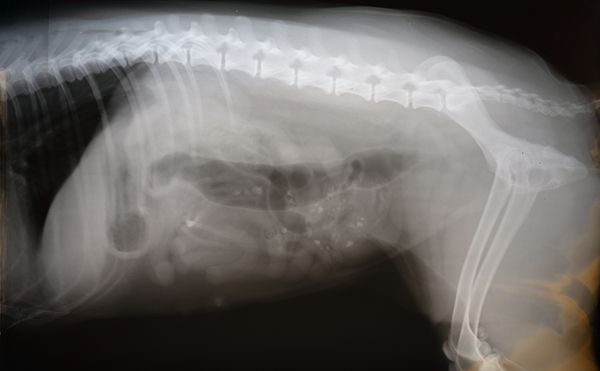

専門検査・高度医療

札幌院では、MRI・CTなどの画像診断装置を用いた精密検査により、

神経疾患や腫瘍(がん)など、より専門的な診断・治療にも対応しています。

一般診療から一歩進んだ医療が可能で、大学や専門機関との連携を取りつつ最善の治療が行える体制を整えています。